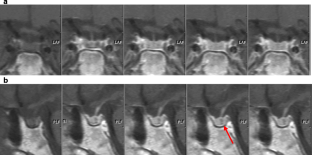

Usefulness of the dynamic gadolinium-enhanced magnetic resonance imaging with simultaneous acquisition of coronal and sagittal planes for detection of pituitary microadenomas

Average scores for lesion detection of a combination of two planes, coronal, and sagittal images were 2.59, 2.32, and 2.18. 6/10 lesions negative on coronal images were detected on sagittal ones. Accuracy of a combination of two planes, of coronal and of sagittal images was 92.86%, 82.14% and 75%. Six patients had probable or definite additional information on supplementary sagittal images compared with coronal ones alone (10.71%).

Dynamic MRI with combined coronal and sagittal planes was more accurate for detection of pituitary microadenomas than routinely used coronal images. Simultaneous dynamic enhanced acquisition can make study time fast and costs low.